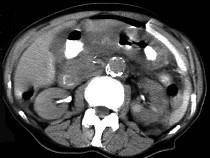

问题 男,44岁,突然中上腹痛,压痛,反跳痛,腹肌紧张,发热,白细胞计数升高,CT检查如图,最可能诊断是 ( )

选项 A、胰腺癌 B、胃癌 C、慢性胰腺炎 D、胃小弯溃疡穿孔 E、急性胰腺炎

答案 D